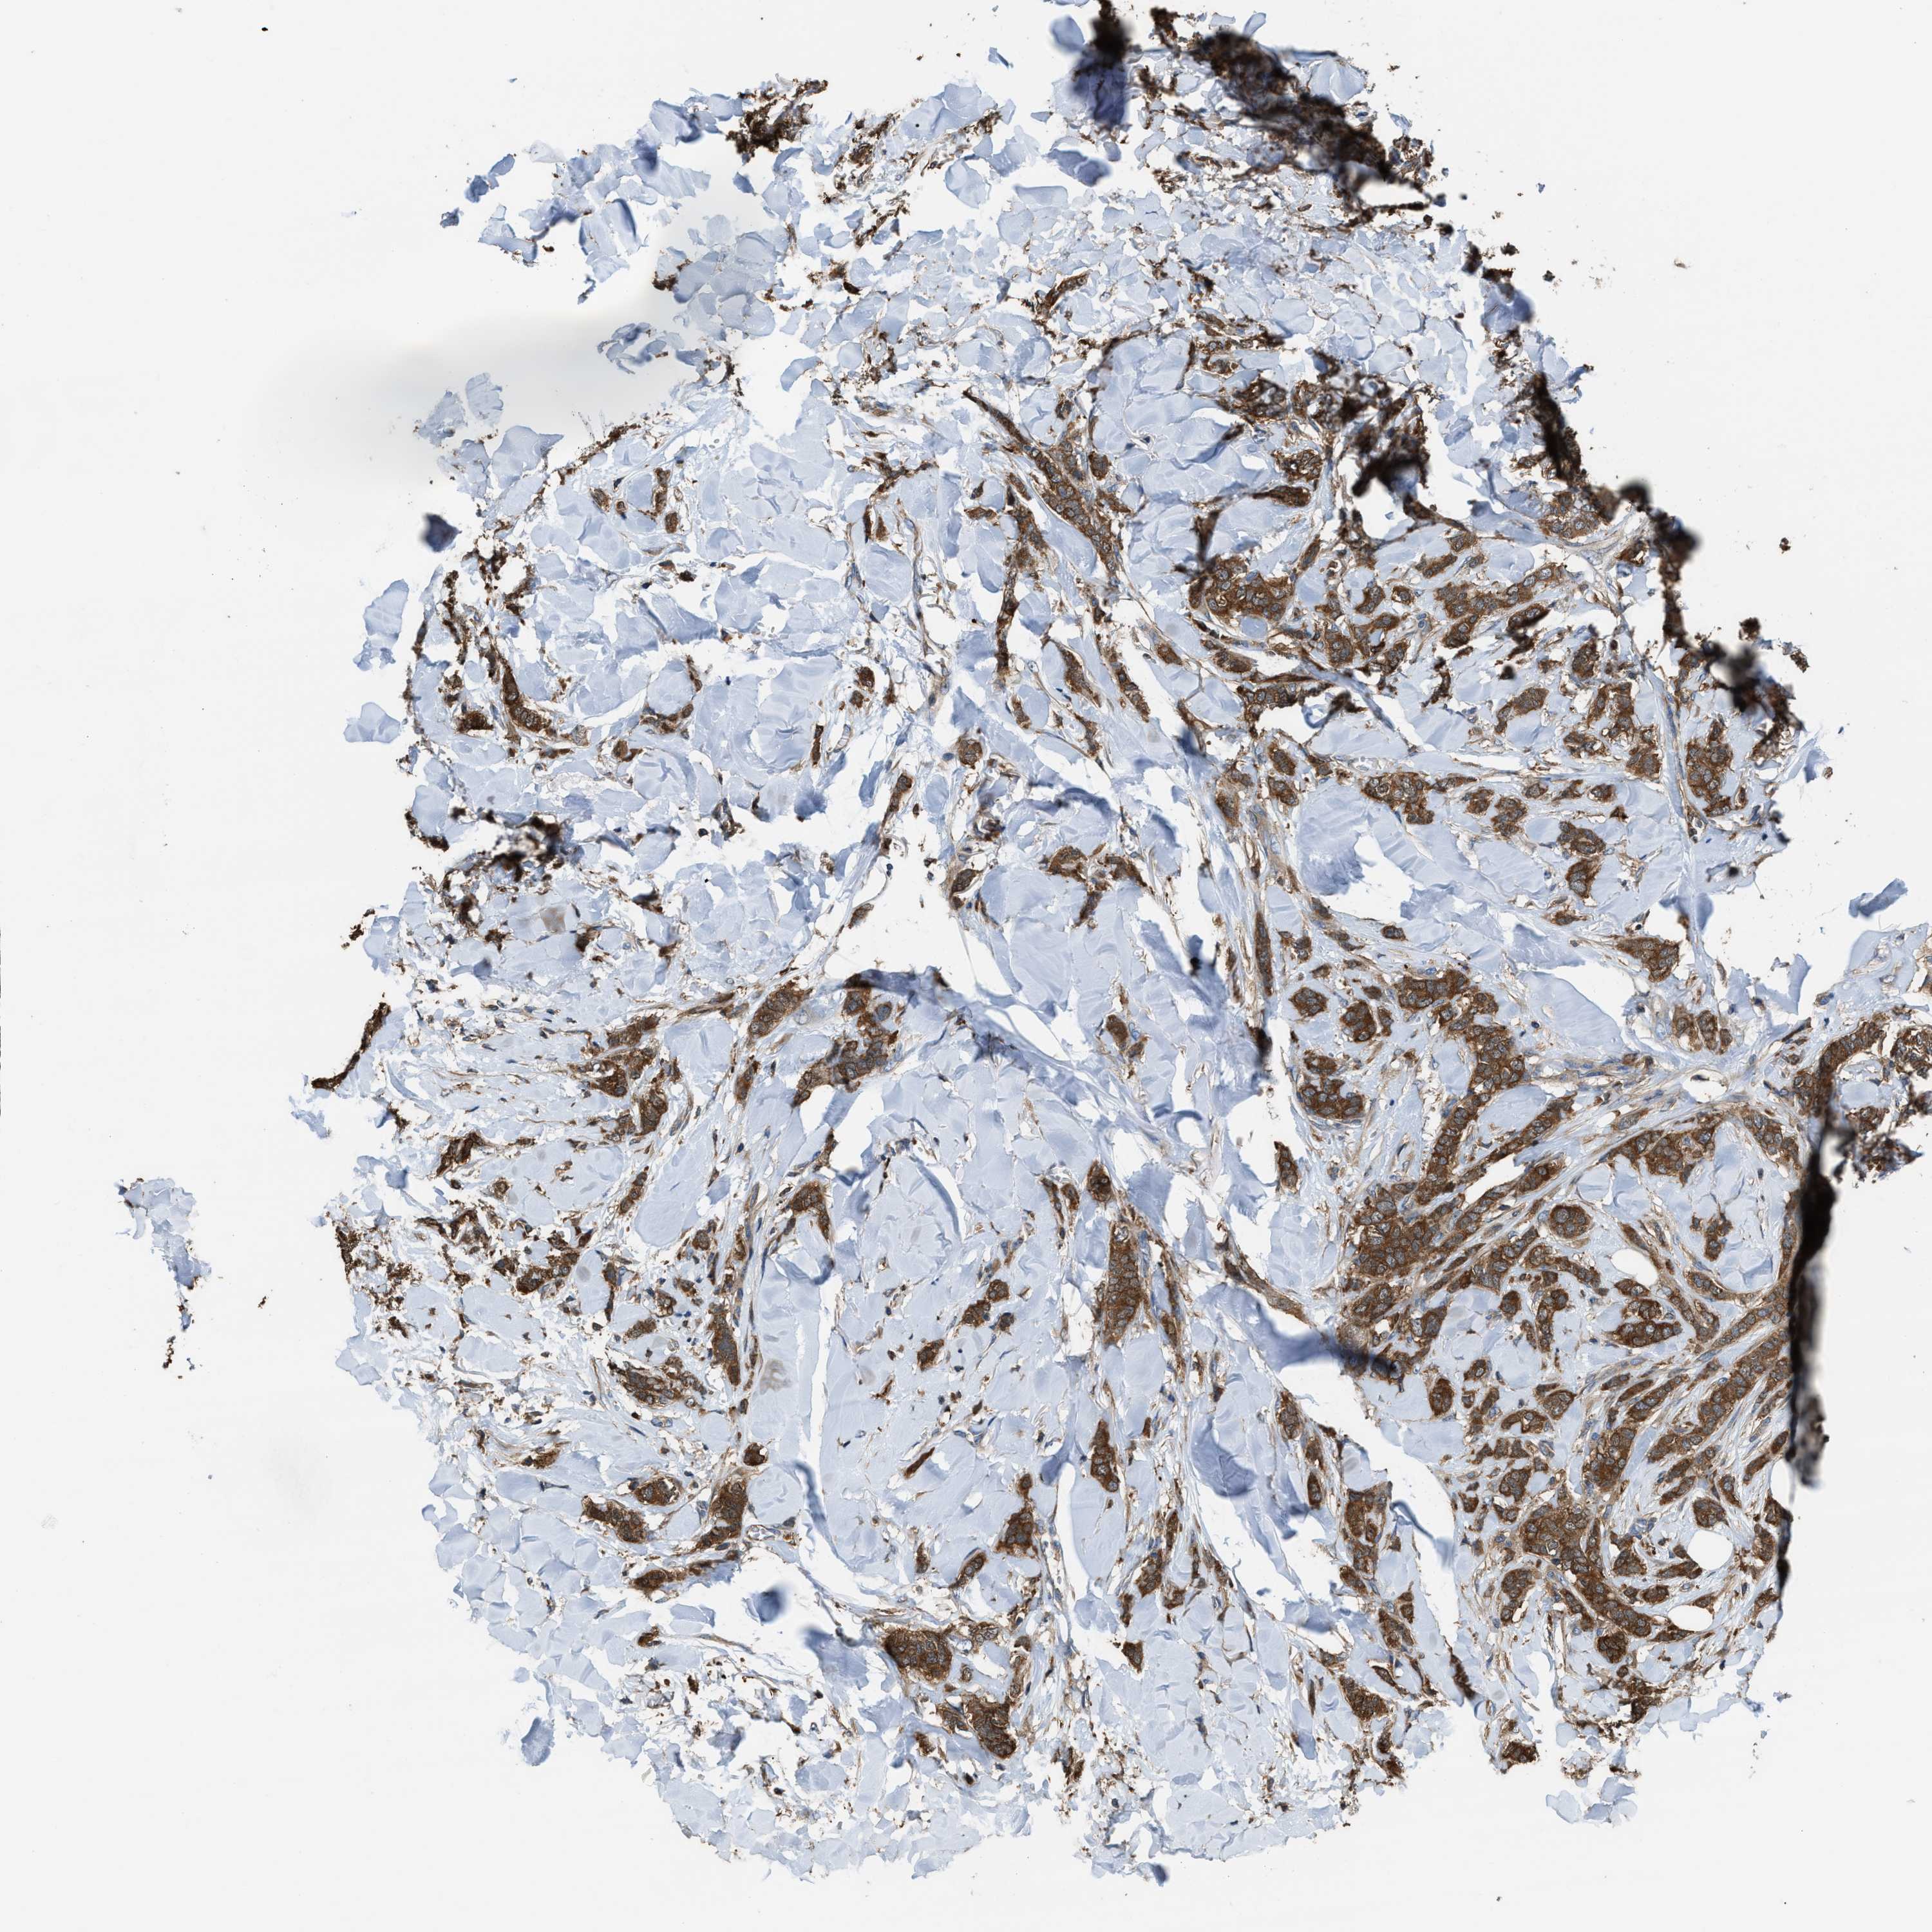

CANCER BREAST CANCER Show tissue menu

BRCA TCGA BRCA VALIDATION PROTEIN EXPRESSION